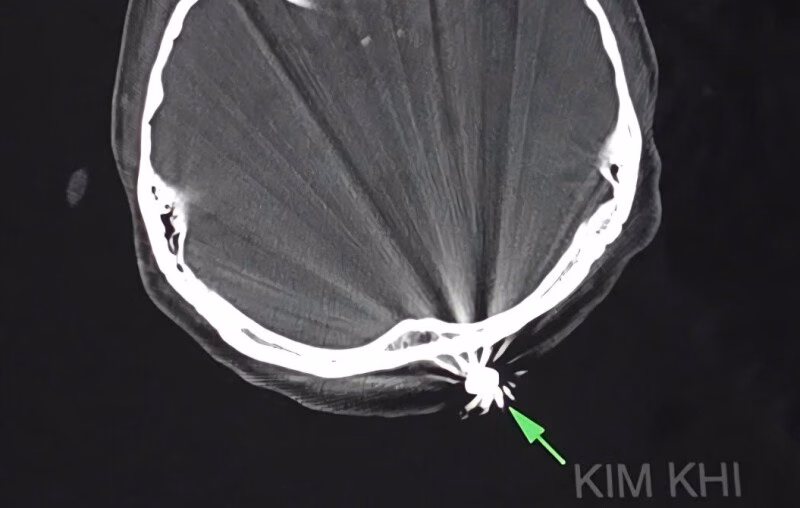

Chị D.T.K.T, cư trú tại TP Cần Thơ, bất ngờ bị trúng đạn vào vùng đầu trong lúc làm vườn tại nhà vào chiều ngày 28/7. Viên đạn đã găm vào vùng chẩm, gây ra chảy máu nhiều. Ngay sau đó, bệnh nhân được đưa đến bệnh viện trong tình trạng đau đầu dữ dội, với một vết thương nhỏ khoảng 1cm ở vùng chẩm đã cầm máu.

Các bác sĩ tại Khoa Ngoại thần kinh của bệnh viện đã nhanh chóng tiến hành phẫu thuật để lấy dị vật và xử trí tổn thương. Quá trình phẫu thuật, các bác sĩ đã mở rộng vết mổ khoảng 3cm để lấy ra dị vật kim khí là đầu đạn có kích thước 0,5×0,3cm. Ca phẫu thuật kéo dài khoảng 45 phút và diễn ra rất thuận lợi.

Điều đáng chú ý trong trường hợp này là viên đạn chỉ xuyên qua lớp da và chạm nhẹ vào xương chẩm, không gây ra tổn thương đến não và các cấu trúc lân cận. Hiện tại, bệnh nhân tỉnh táo, tiếp xúc tốt, vết mổ khô và không có triệu chứng thần kinh khu trú.